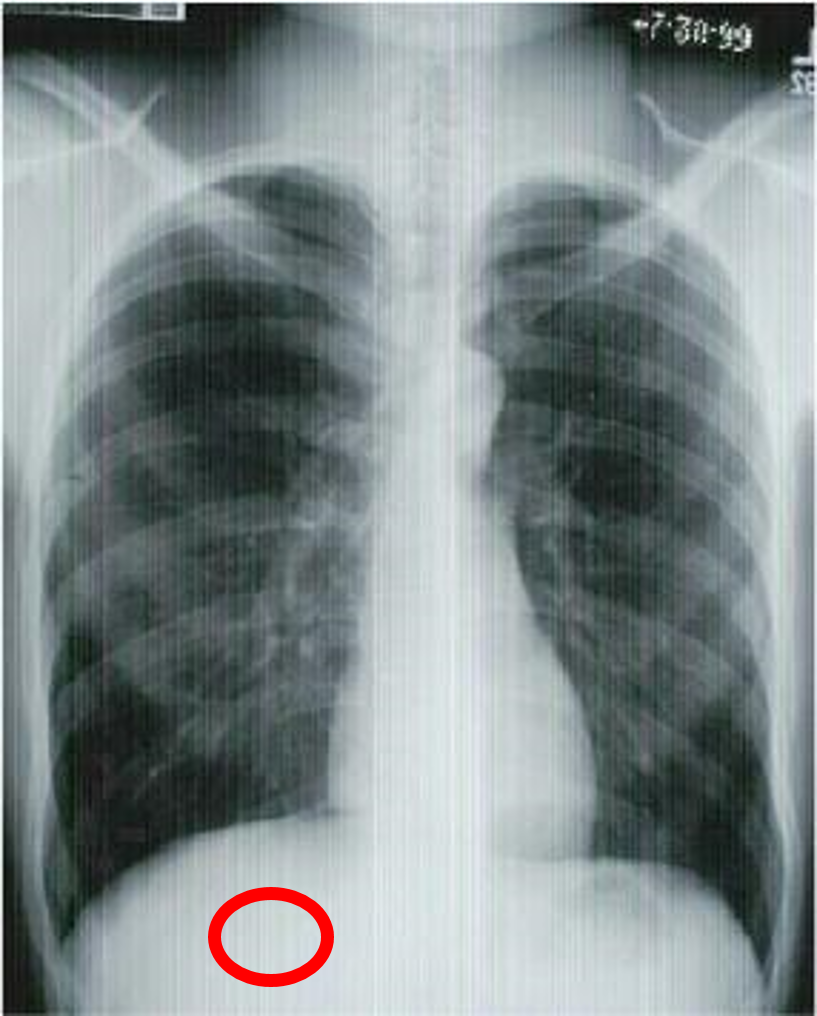

what view is this?

give three indicators

PA chest

aortic arch

diaphragm

left ventricle

liver

pulmonary artery

right atrium

right mainstem bronchus

stomach

trachea